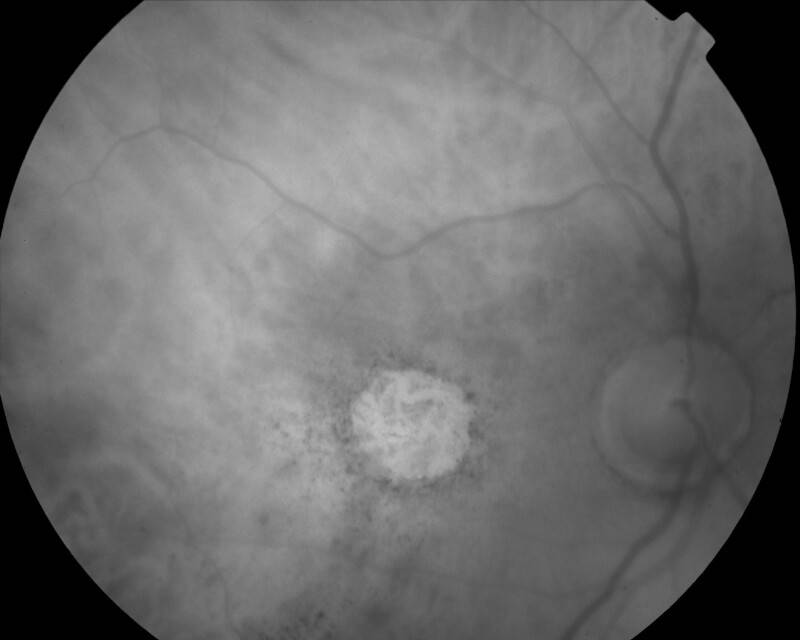

ATROPHIE AREOLAIRE CENTRALE

IMG0007.jpg